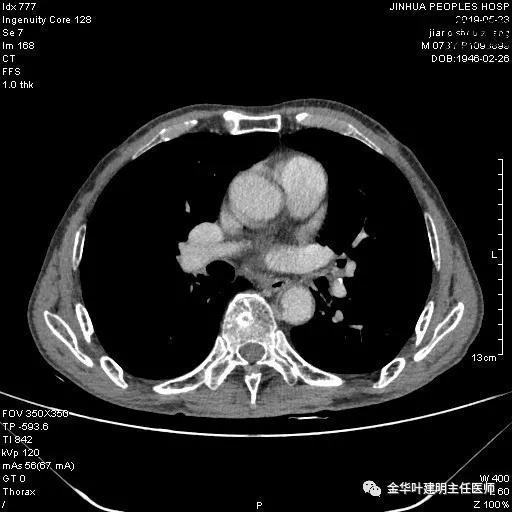

考虑左侧大量胸腔积液,遂进一步胸部CT检查:

以上是肺窗表现,下面为纵隔窗影像: